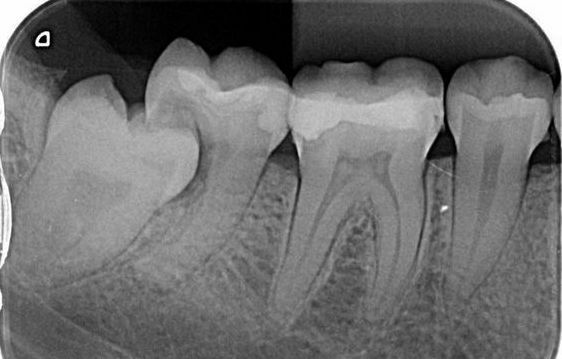

Когда необходимо удаление зуба?

- Тотальное разрушение коронковой части зуба. Не представляется возможным восстановить зуб пломбой, накладкой, коронкой. При этом зуб открыт и является входными воротами инфекции.

- Кариес корня зуба. В этом случае невозможно гарантировать достаточную функцию зуба после лечения.

- Подвижность зуба III степени. При пародонтите, пародонтозе связки зуба разрушаются и восстановить их невозможно.

- Ретенция зубов мудрости. Приводит к воспалению, окружающих зуб, мягких тканей, хронической травме слизистых оболочек полости рта, к смещению других зубов, кариесу и осложнениям кариеса рядом стоящих зубов.

- Наличие хронических очагов воспаления. Возникновение обширных гранулематозных образований на кончиках корней зубов, которые не подлежат повторному эндодонтическому лечению.